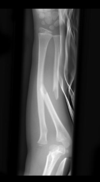

Cisto ósseo simples com fratura

Lesão litica unicameral.

Localização: úmero proximal e femur (< 20 anos) ou calcâneo, talus, ileo (> 20 anos).

Se fratura: Sinal do fragmento caído.